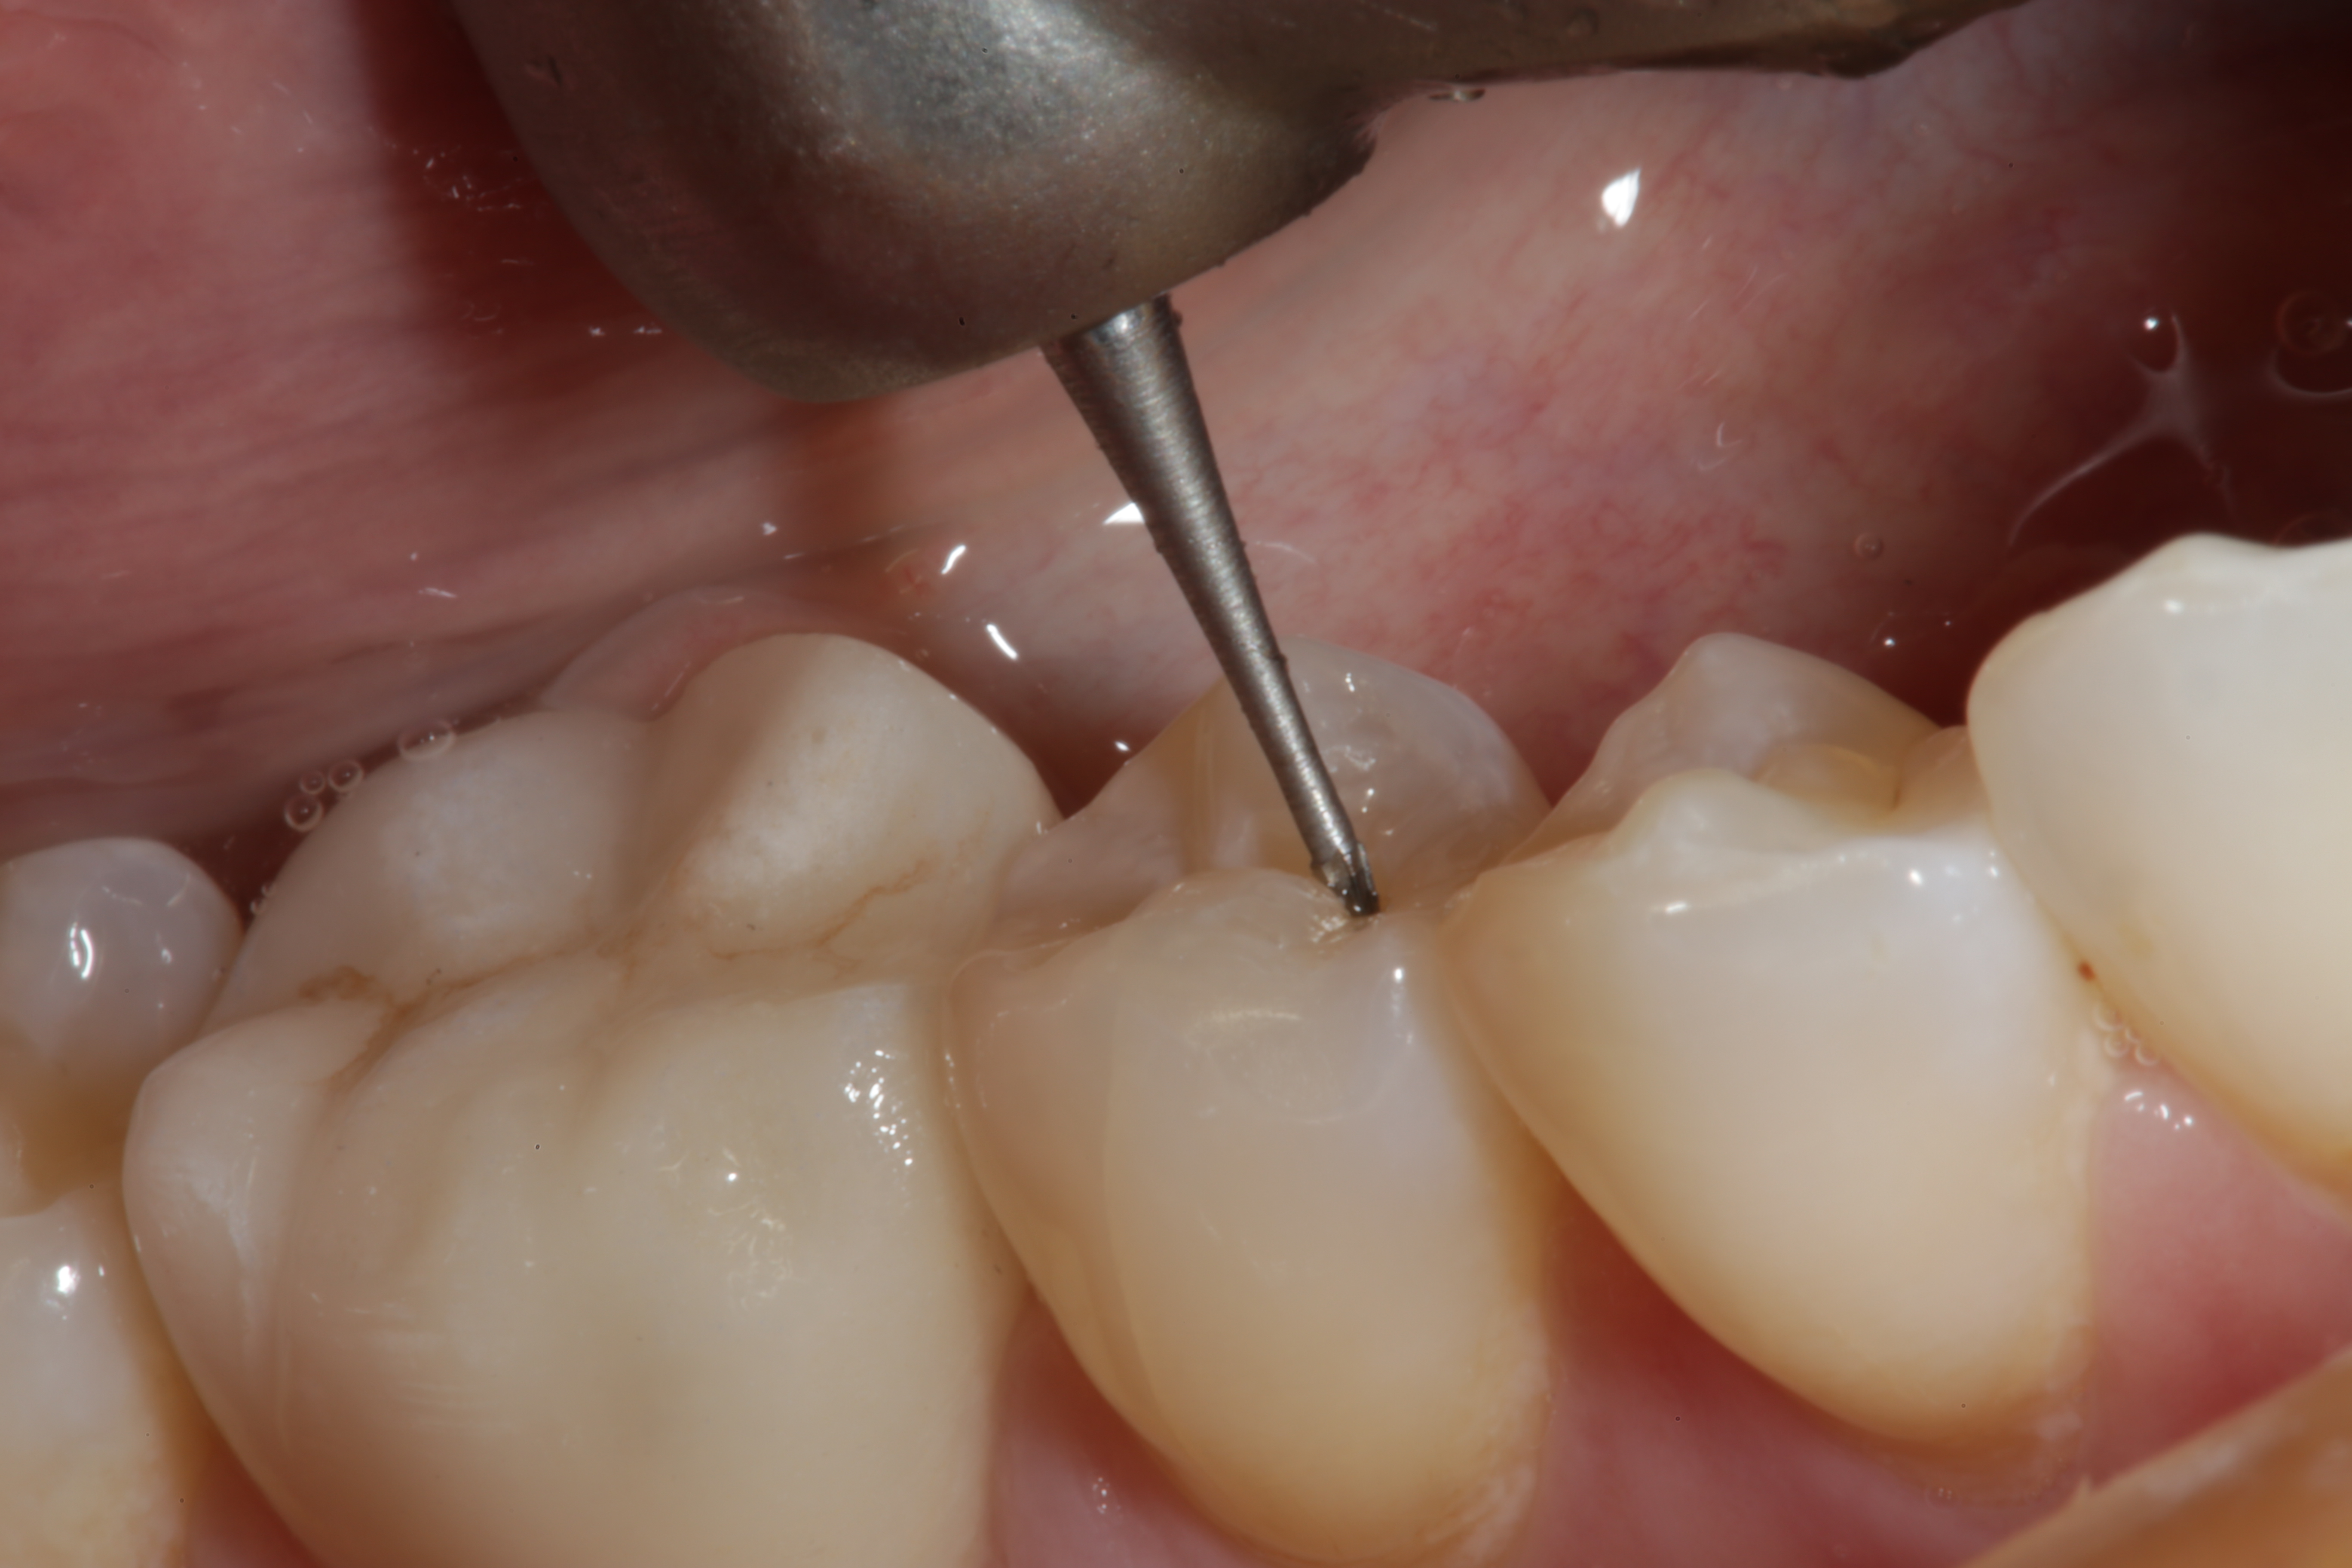

Fig 2. A Fissurotomy bur is used to remove decay found in the central groove of this mandibular premolar.

Figure 2